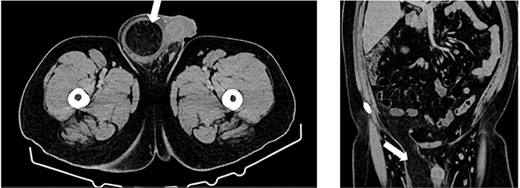

A 27-year-old male presented to the emergency department with acute scrotal pain for 48 hours. He has been having 1-week history of ongoing dull right testicular pain, was diagnosed with epididymal orchitis by his general practitioner and given a week of Augmentin Duo Forte (DF). He denied any history of cryptorchidism. He also has a large right inguinal hernia containing omentum that has been present for 1 year and was awaiting elective repair. Forty-eight hours prior to presentation, his 2-year-old, 20 kg son kicked him in the scrotum. He denied any abdominal pain, dysuria or hematuria. On examination, his right hemiscrotum was grossly swollen, with midline shift of the scrotum, a palpable inguinoscrotal hernia, erythematous, absent cremasteric reflex and a difficult to palpate right testicle. His left testicle had normal examination. He had an urgent scrotal ultrasound (US) showing reduced vascularity of the right testicle, query ischemia (Fig. 1). He then had a computed tomography abdomen and pelvis with contrast showing a large right indirect inguinal hernia containing fat (Fig. 2). On examination, his right hemiscrotum was grossly swollen, with midline shift of the scrotum (Fig. 3), a palpable inguinoscrotal hernia, his scrotum was erythematous, with an absent cremasteric reflex, and a difficult to palpate right testicle. His left testicle had normal examination. He underwent a scrotal exploration with findings of sliding right inguinal hernia with large amount of very stuck and strangulated omentum. The right testicle was found to be infarcted, multiple stabs of the testicle revealed no perfusion, turbid fluid was also noted and the head of the epididymis was necrotic (Fig. 4).

Computed tomography (CT) axial and coronal imaging showing large fat-containing right inguinal hernia (white arrow).